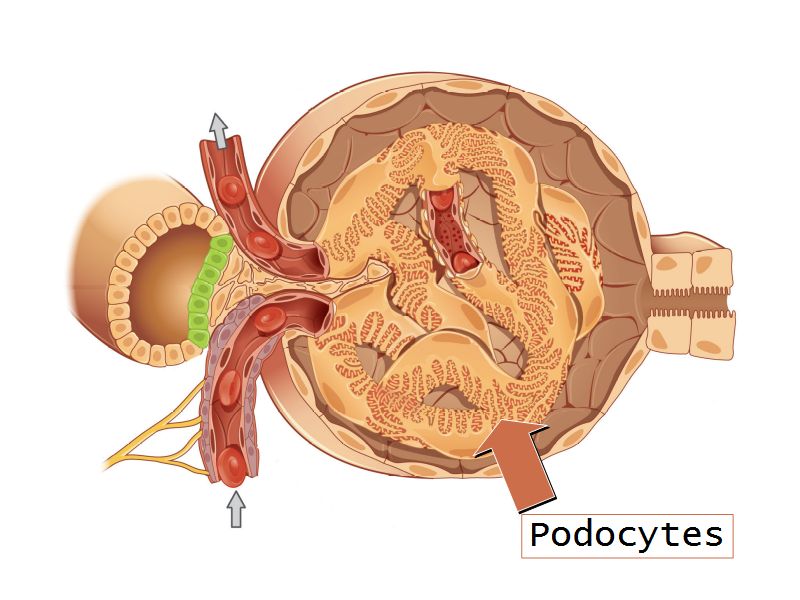

Visceral layer of epithelium

Podocytes

Resting on glomerular basement membrane